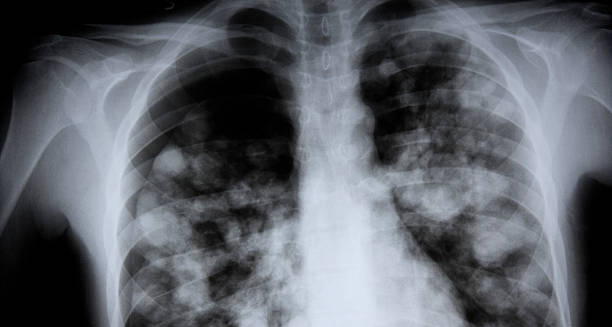

3. Chest X-Ray | Diagnosis of Chest Infection

A chest X-ray is often used to detect pneumonia and differentiate it from bronchitis or other lung conditions. Pneumonia appears as areas of opacity or consolidation on the scan.